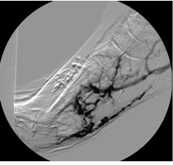

As in many cases, the patient presented with a relatively small (0.5cm x 0.5cm x 0.2cm) DFU under the first metatarsal on the right foot (Figure 1a, b). Over 2 months, the DFU did not close, instead, it grew with increasing depth to 0.4cm and developed osseous involvement. On her second hospitalization there was concern of DFU infection, and she underwent vascular imaging to assess the extent of her peripheral arterial disease (PAD). Her ankle brachial indices (ABIs) were falsely elevated due to her comorbidities and toe pressure was less than 40mmHg (Figure 2). Duplex ultrasound showed significant mural calcification of the tibial arteries of the right calf with occlusion of the right posterior tibial artery in the proximal calf and the right anterior tibial and peroneal arteries in the distal calf. Angiogram demonstrated severe tibial disease not amenable to endovascular interventions with no bypass target available (Figure 3). As described in the article by Montero-Baker and colleagues,10 given her occluded anterior tibial artery and suitable great saphenous vein, she underwent a hybrid superficial venous arterialization for limb salvage (Figure 4).

Post-surgical intervention, she continued aggressive local wound care while the SVA matured with biweekly follow-ups with vascular or podiatry. The VA circuit typically takes 4-6 weeks for maturation, during which time the new circuit powers the collateral circulation and tissues to achieve adequate oxygen delivery from the new arterialized vein.8 Prior to partial foot amputation, the patient had a repeat angiogram to detect any changes in blood flow that could jeopardize the patency of this reconstruction and, consequently, impair wound healing. The test revealed adequate perfusion.